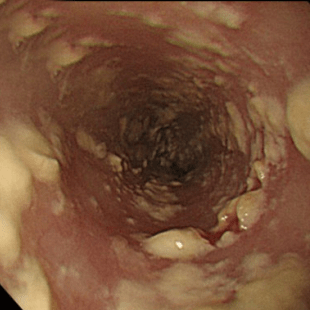

Фибринозный (псевдомембранозный) эзофагит. Наблюдают бело-серые или бело-желтые рыхлые налеты в виде округлых бляшек диаметром от 1 до 5 мм, выступающие над ярко гиперемированной и отечной слизистой оболочкой. Контактная ранимость и гиперемия слизистой оболочки заметно выражены.

Фибринозно-эрозивный эзофагит. Характерно наличие грязно-серых «бахромчатых» налетов в виде «лент», расположенных на гребне продольных складок пищевода. При инструментальном отделении таких налетов обнажается эрозированная слизистая оболочка. Эрозии могут быть округлой или линейной формы, размерами чаще от 0,1 до 0,4 см в диаметре. Слизистая оболочка пищевода крайне ранима, отечна и гиперемирована. Выраженные изменения слизистой оболочки иногда препятствуют полноценному эндоскопическому осмотру пищевода (кровотечение, боль и беспокойство пациента, стеноз пищевода, вызванный отеком) [2].

- Фибринозно-эрозивный эзофагит. Кандидоз проявляется множественными налетами грязно-серого цвета, после удаления которых на слизистой оболочке визуализируются эрозии. Характерна спонтанная кровоточивость.

Степень III: Сливные линейные и узловатые приподнятые бляшки, с гиперемией и язвами

Степень IV: Те же изменения, что и при III степени, плюс контактная кровоточивость слизистой оболочки и иногда сужение просвета пищевода

При гистологическом исследовании биопсийного материала из пораженных участков видны дрожжевые грибы с псевдогифами, проникающими в эпителиальный слой слизистой оболочки. Иногда отмечается проникновение микроорганизма в глубокие слои стенки органа.